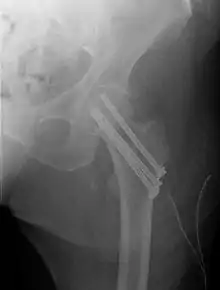

Intertrochanteric hip fracture in a 17-year-old male

A hip fracture is a break that occurs in the upper part of the femur (thigh bone), at the femoral neck or (rarely) the femoral head.[2] Symptoms may include pain around the hip, particularly with movement, and shortening of the leg.[2] Usually the person cannot walk.[3]